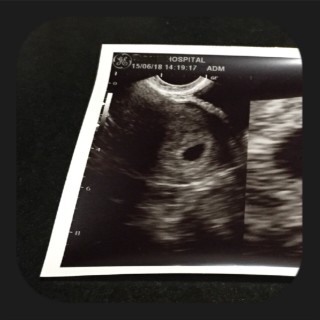

ドキドキしながら病院に行くと すぐに胎嚢が確認出来ました。 大きさは教えてもらえませんでしたが、 いい大きさだね、安心して。 と言っていただきました(*^^*) 2週間後が待ち遠しい~